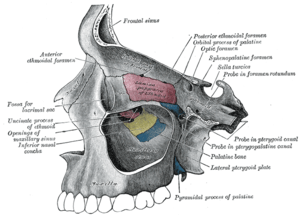

Sagittal section of skull. Roof, floor, and lateral wall of left nasal cavity.

Roof, floor, and lateral wall of left nasal cavity. Nasal bone